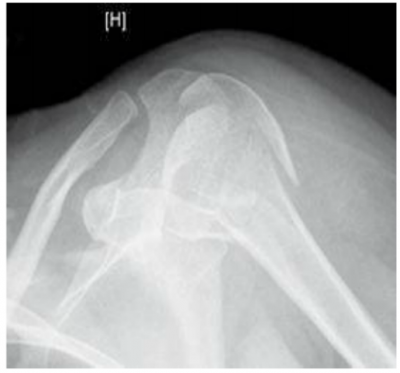

שברים בעצמות הכתף

שברים בכתף מתרחשים עקב חבלה ישירה או עקב חבלה עקיפה בעקבות נפילה. את שברי ראש עצם הזרוע נהוג לחלק לפי מספר חלקי השבר (שני חלקים, שלושה וארבעה). ככל שמספר החלקים ומידת תזוזתם עולים, עולה גם מורכבות השבר. ניתן לטפל בשברים בכמה שיטות. במידה ותזוזת חלקי השבר מזערית השיטה המועדפת היא הגישה השמרנית, הלא ניתוחית, הנותנת דגש על טיפול תמיכתי בכאב ופיזיותרפיה. בגישה הניתוחית, ניתן לקבע את השבר בניתוח מינימלי, ללא פתיחה של השבר, על די החדרת מסמרים ארוכים או ברגים דרך העור, בדרך כלל עם תוספת של קיבוע חיצוני לייצוב השבר. במקרים אחרים יש צורך לחשוף את השבר בניתוח ולחבר חזרה את כל חלקי השבר בעזרת ברגים, ולעיתים גם פלטת מתכת.

במקרים שהסיכוי להחלמת השבר בצורה שתאפשר תפקוד הוא נמוך, יש לשקול החלפה של העצם בתותב ממתכת. במקרים יחודיים של שברים עם תלישת גידים ניתן לתקנם ארטרוסקופית תוך איבחון וטיפול בפגיעות נוספות כגון קרעי גידים ורצועות.

| תמונה 2. חיבור שבר בכתף, תמונה עליונה לפני, תמונה תחתונה אחרי |

בקרב מבוגרים שברי הכתף הם בעיקר של ראש עצם הזרוע ונגרמים עקב אוסטאופורוזיס. בגיל הצעיר השברים האופיינים הם של עצם הבריח (Clavicle) והסובב אותה לרוב כתוצאה מחבלות משמעותיות או כתוצאה מפריקת כתף. השברים יכולים להיגרם בצורה ישירה או עקיפה, כגון נפילה על המרפק או על שורש כף היד.

בשברי עצם הבריח הטיפול השמרני מוצלח לרוב ורוב החולים ייהנו מחזרה לתפקוד מלא. שברים עם תזוזה משמעותית עלולים להוביל לאי חיבור בכ-30 אחוזים מהמקרים ולתפקוד לקוי של הכתף. במקרים אלו נדרש טיפול ניתוחי שכולל שחזור חלקי השבר וקיבועו, לרוב בעזרת פלטה וברגים.